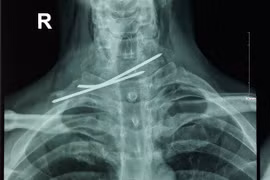

(GLO)- Một người đàn ông ở Quảng Bình bị cây đinh dài 7 cm đâm vào đầu hơn 1 năm mà không biết. Gần đây bệnh nhân có nhiều biểu hiện bất thường nên được đưa tới bệnh viện huyện thăm khám mới phát hiện.